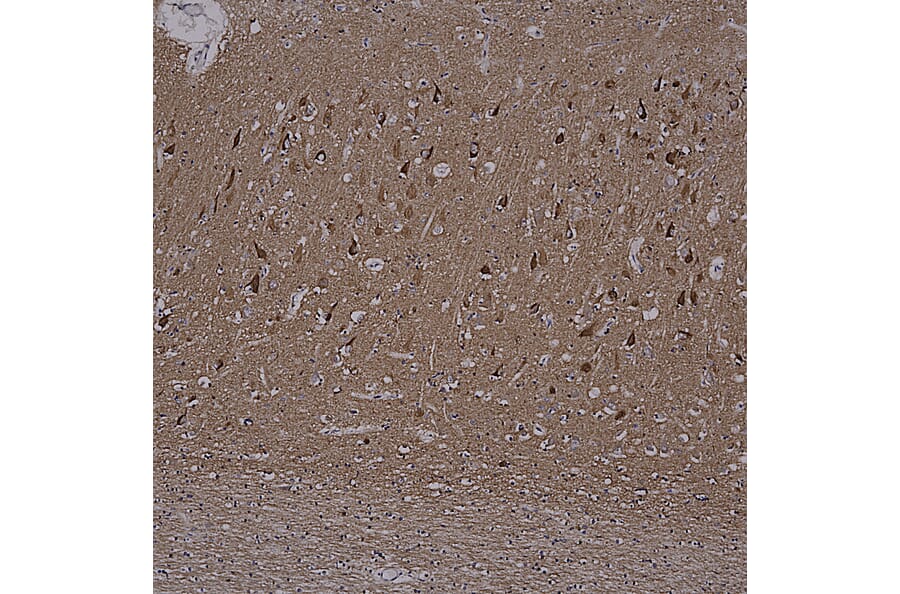

Immunohistochemistry analysis of a NBF fixed paraffin embedded human brain hippocampus section from an Alzheimer’s Disease case. Mouse mAb to MAPtau, Anti-Tau Antibody [2E9] (A85416) at a dilution of 1:1,000, was detected in DAB (brown) using the Vector Labs ImmPRESS method and reagents with citra buffer retrieval. Counterstained with Hematoxylin (blue). The Anti-Tau Antibody [2E9] (A85416) strongly labels cell bodies in diseased neurons and is ubiquitously expressed at a lower level in most cells types. Note: this antibody performs well in testing with 4% PFA or standard NBF fixed human and rat tissues.